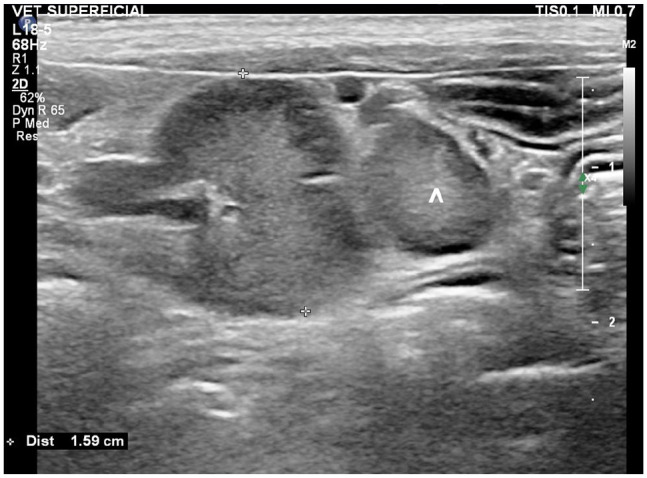

Case summary: A 6-year-old male castrated Maine Coon cat was presented with a 3-day history of lethargy, hyporexia and weight loss. Abdominal ultrasonography demonstrated a double intestinal intussusception with the colon intussuscepting a thickened ileal segment, which was in turn intussuscepting the jejunum. A jejunal prolapse through the anus occurred 3 days later as a complication of the double intussusception, at which time the cat underwent surgery. Manual reduction of part of the intussusception was achieved, while the remaining 30 cm, including of the ileocaecocolic junction, was resected followed by functional end-to-end anastomosis. The cat recovered uneventfully without any reported long-term gastrointestinal complications.

Relevance and novel information: Double intussusception is rare in cats. To the best of the authors' knowledge, this is the first case to describe ultrasonographic features of double intussusception in a cat.